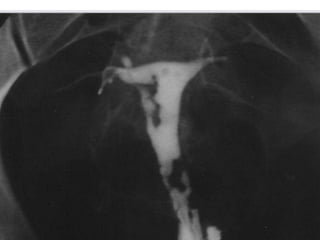

• Hydrosalpinx

• Common cause- salpingitis

• Distal tubal occlusion- dilatation of proximal

segment

• Hydrosalpinx • Commoncause- salpingitis • Distal tubal occlusion- dilatation of proximal segment

• #44 Commonly results from previous inflammation of fallopian tubes(salpingitis) Distal tubal occlusion- dilation of proximal segment Dilated lumen, contrast will not pass in to the pleural cavity